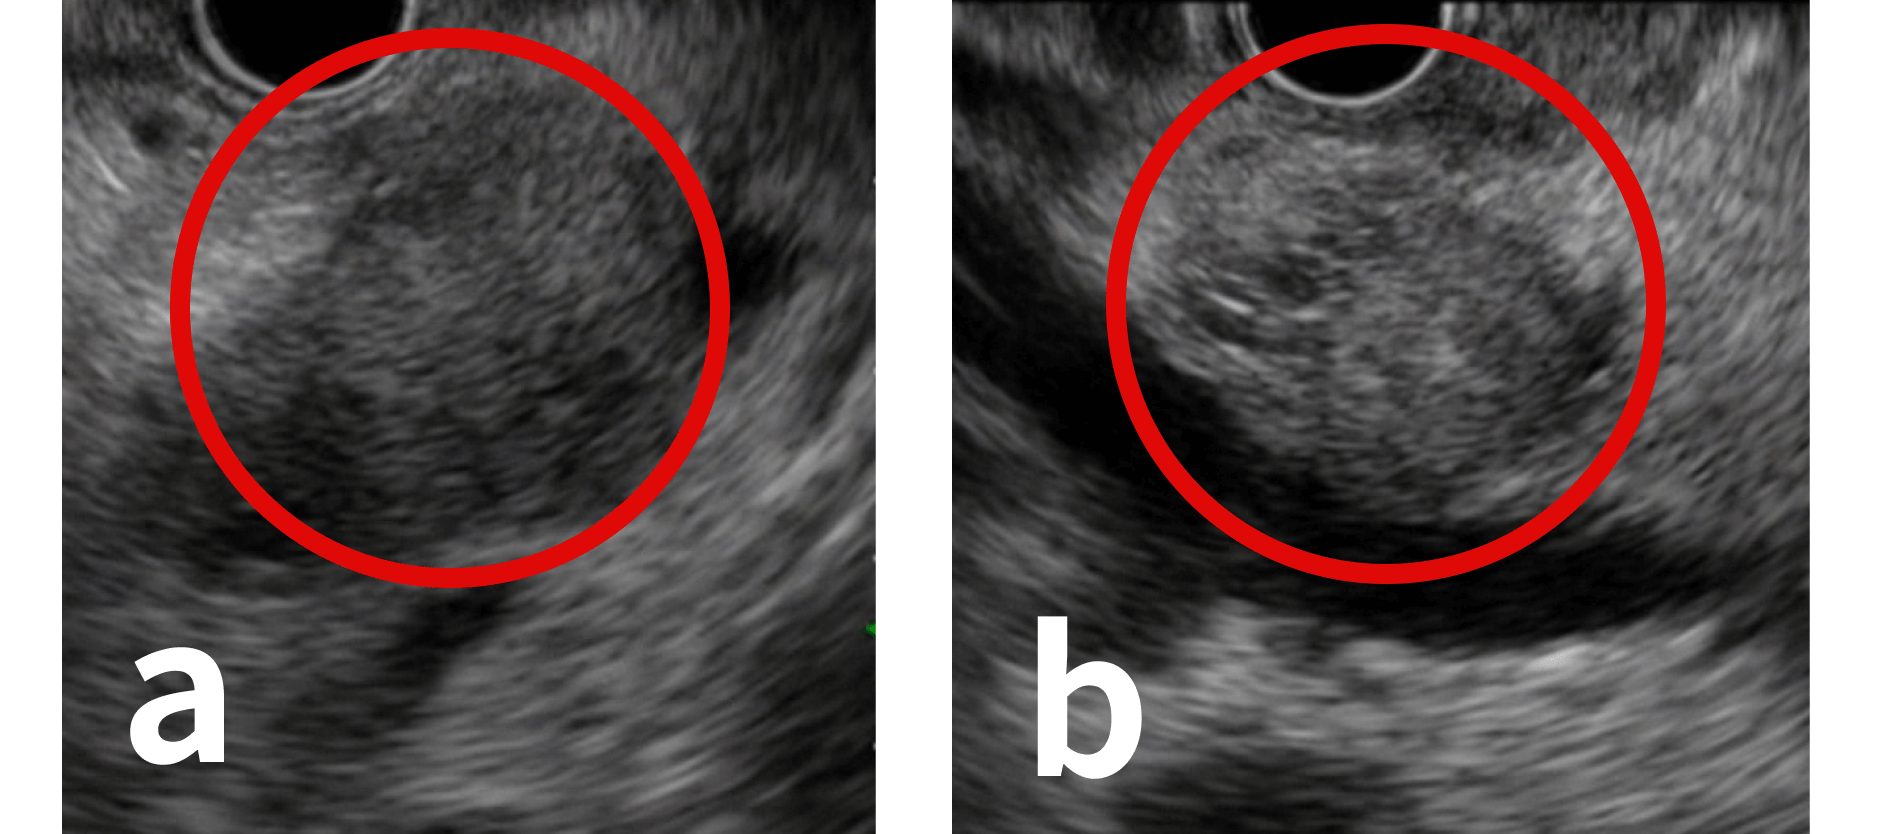

当院では、膵臓がんの早期発見のために、MRI検査、超音波検査、CT検査などを行い、それらの検査で膵臓がんが疑われる患者さんには、超音波内視鏡(EUS)検査を行います。EUSとは、先端部分から超音波を発する特殊な内視鏡ですが、胃カメラと同じ方法で行うため侵襲性が少ないのが特徴です。口から挿入し、食道から胃、十二指腸の消化管壁を通して、内臓の奥深くにある膵臓を超音波で観察することができます。EUSは膵臓全体(膵頭部、膵体部、膵尾部)の状態を細部まで見ることができるため、CT検査やMRI検査などの他の検査よりも数mm~2cm以下程度の小さな膵臓がんも見つけられる可能性が高まります。

膵臓がんのEUS画像(各々約2cm)

a.胃を介して描出した膵体部がん

b.十二指腸を介して描出した膵頭部がん

EUSでさらに膵臓がんが疑われた場合は、EUSの先端から穿刺針を出し、対象部位に穿刺し組織を採取する超音波内視鏡下穿刺吸引法(EUS-FNA)を行い、病理診断を行います。